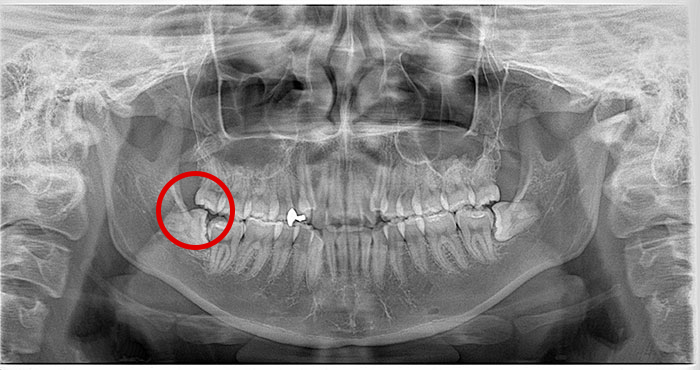

親知らずの症例

Before

After